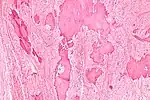

Low magnification micrograph of a calcified ovarian fibroma in the context of nevoid basal cell carcinoma syndrome. H&E stain.

On gross pathology, they are firm and white or tan. On microscopic examination, there are intersecting bundles of spindle cells producing collagen.

There may be thecomatous areas (fibrothecoma). The presence of an ovarian fibroma can cause ovarian torsion in some cases.